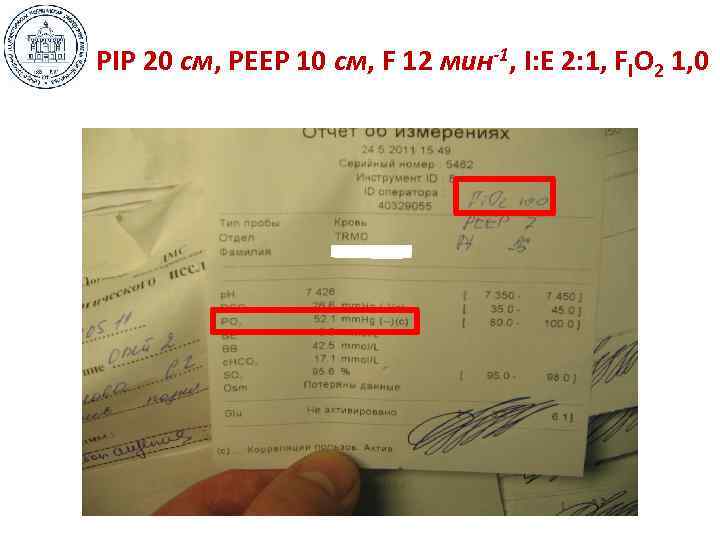

• • • Маневр раскрытия: пошаговая методика Режим – Pressure Control Ставим PEEP = 15 -25 см Н 2 О, PIP = 10 -15 см Н 2 О Измеряем исходное Ра. О 2 Находим точку раскрытия: увеличивая PIP на 3 см Н 2 О каждые 5 -10 мин, находим начало плато Ра. О 2 Находим точку закрытия: уменьшая РЕЕР на 3 см Н 2 О каждые 5 -10 мин, находим начало снижения Ра. О 2 Выставляем PIP на уровне точки раскрытия, РЕЕР на 3 см Н 2 О выше точки закрытия Контрольная цифра: ДО д. б. на уровне 6 -8 мл/кг Если ниже – увеличиваем PIP, если выше – повышаем РЕЕР Регулируем FIO 2 на величину Ра. О 2 ≤ 110 -115 мм Hg Высокое FIO 2 менее опасно, чем механическая травма!

• • • Маневр раскрытия: пошаговая методика Режим – Pressure Control Ставим PEEP = 15 -25 см Н 2 О, PIP = 10 -15 см Н 2 О Измеряем исходное Ра. О 2 Находим точку раскрытия: увеличивая PIP на 3 см Н 2 О каждые 5 -10 мин, находим начало плато Ра. О 2 Находим точку закрытия: уменьшая РЕЕР на 3 см Н 2 О каждые 5 -10 мин, находим начало снижения Ра. О 2 Выставляем PIP на уровне точки раскрытия, РЕЕР на 3 см Н 2 О выше точки закрытия Контрольная цифра: ДО д. б. на уровне 6 -8 мл/кг Если ниже – увеличиваем PIP, если выше – повышаем РЕЕР Регулируем FIO 2 на величину Ра. О 2 ≤ 110 -115 мм Hg Высокое FIO 2 менее опасно, чем механическая травма!

РIP 20 см, РЕЕР 10 см, F 12 мин-1, I: E 2: 1, FIO 2 1, 0

РIP 20 см, РЕЕР 10 см, F 12 мин-1, I: E 2: 1, FIO 2 1, 0